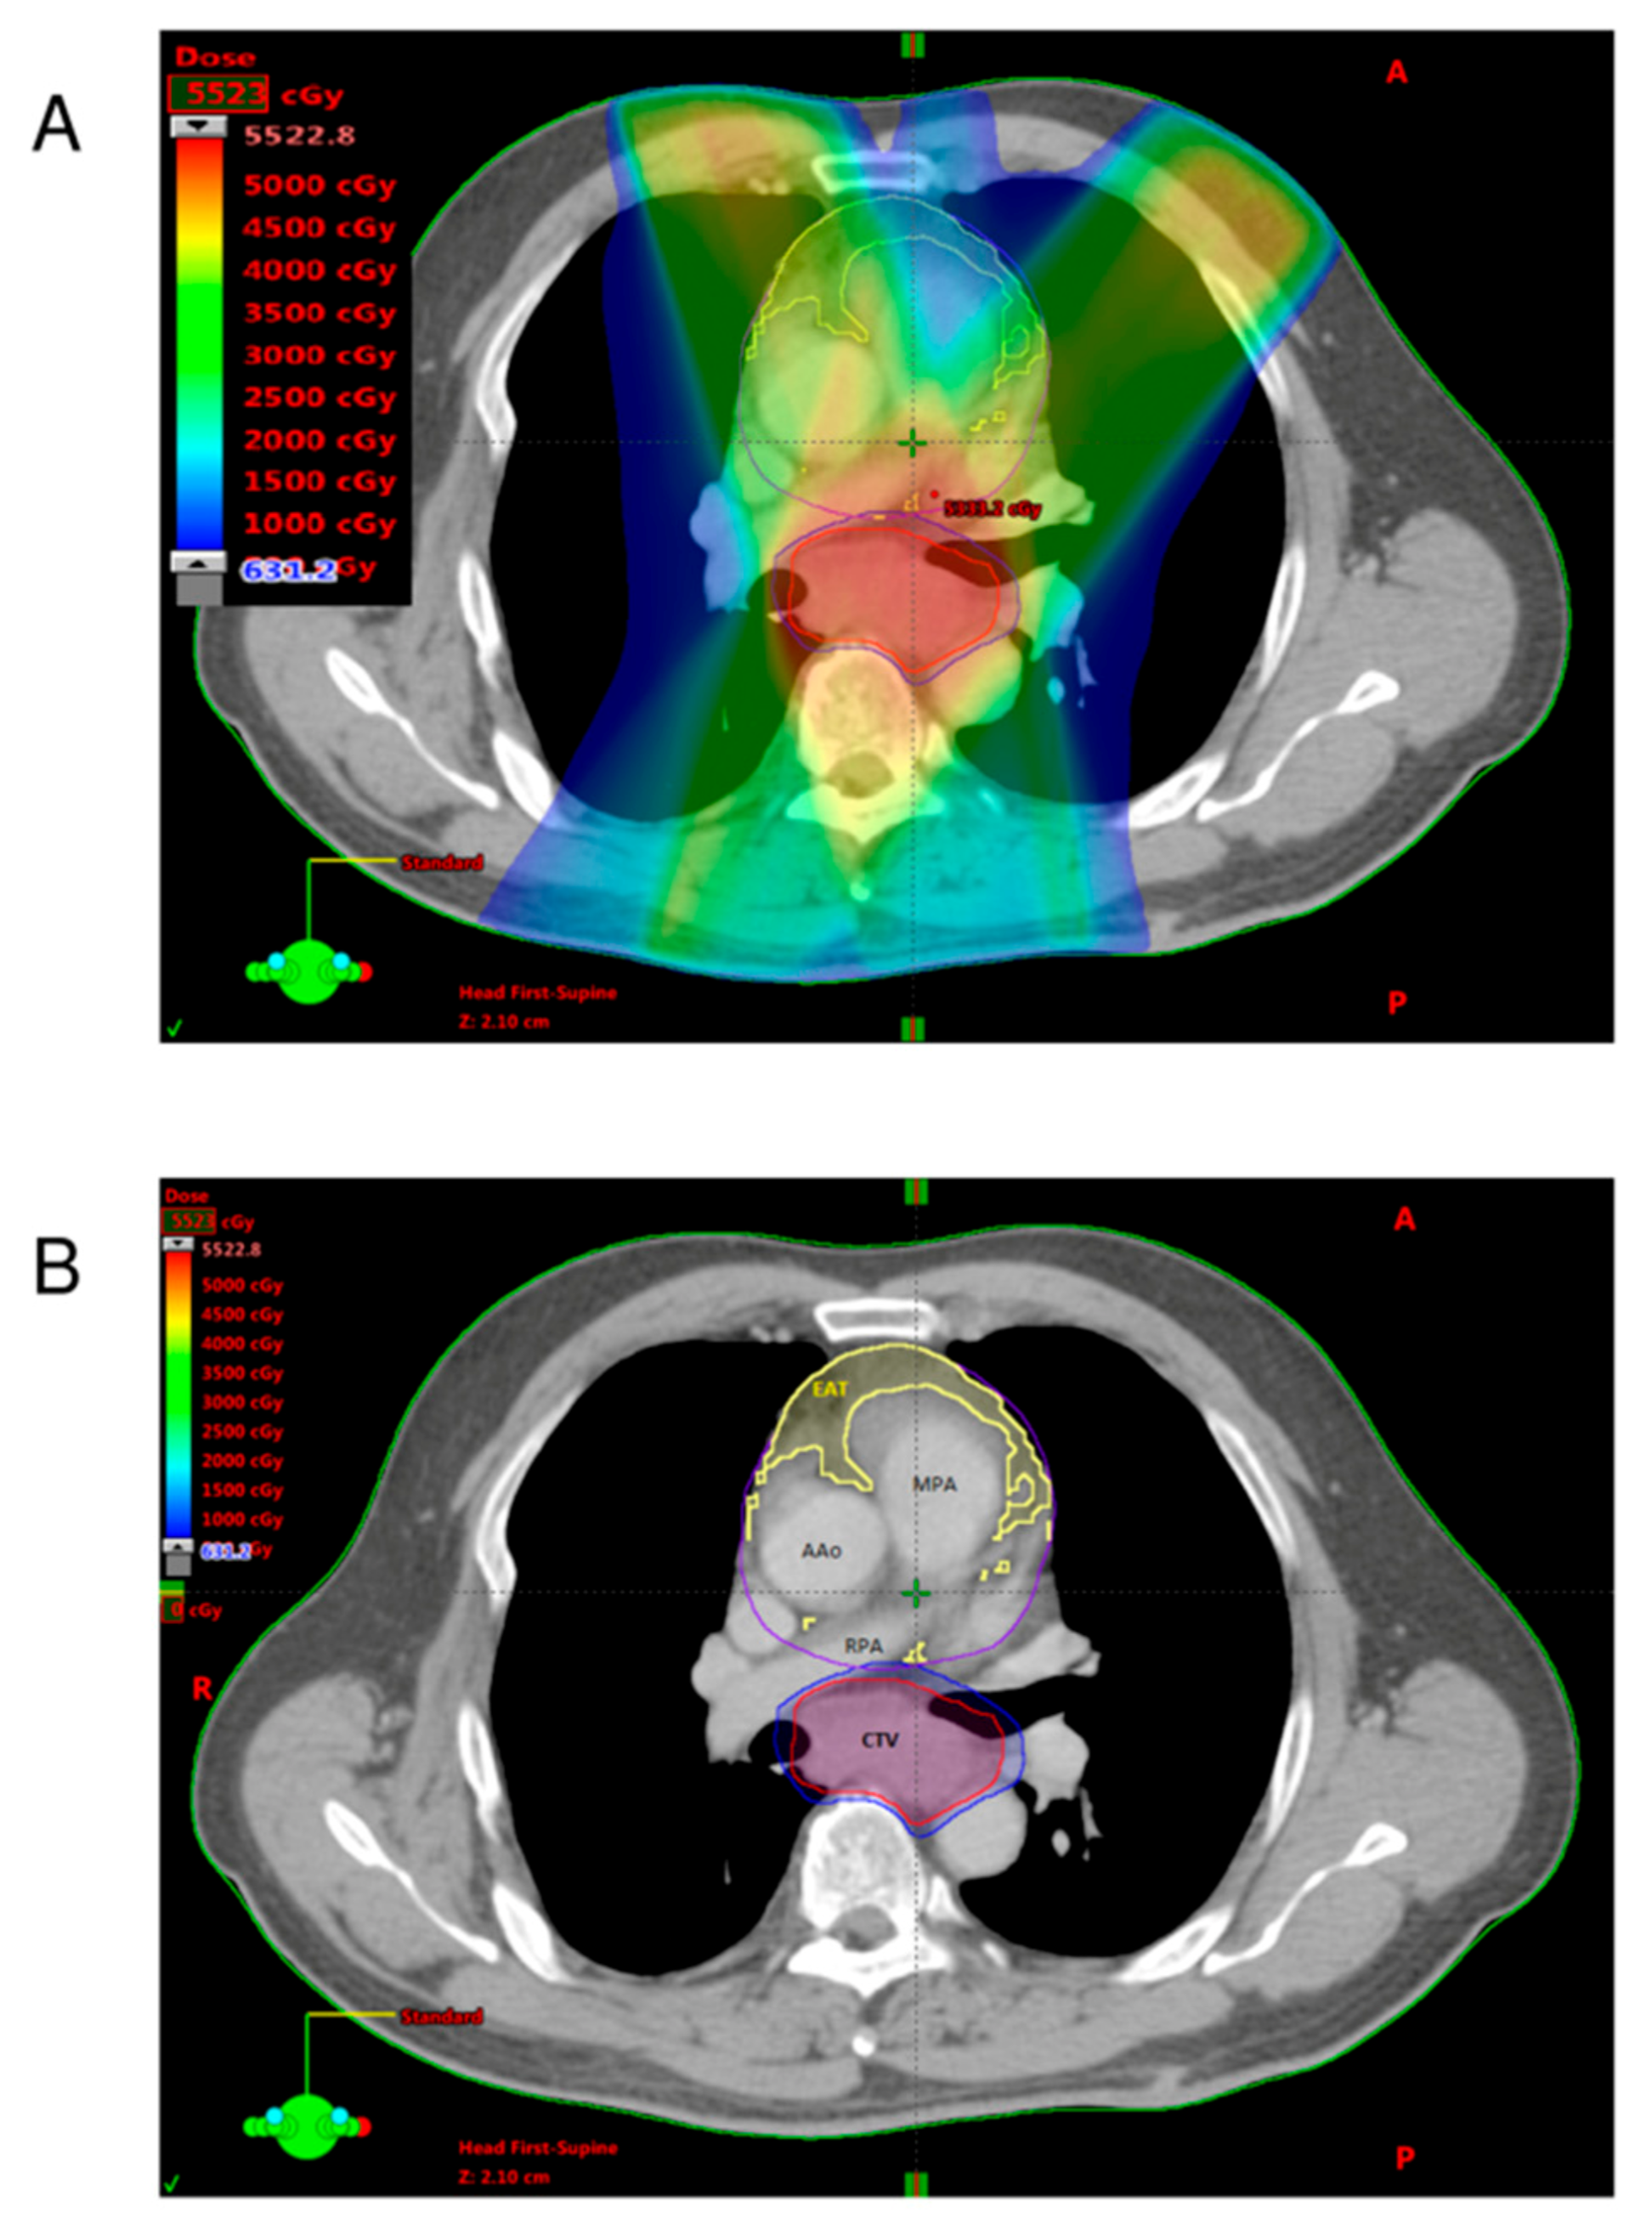

2.3. Quantification of Adipose Tissues

2.4. Definition of EAT-REI

3.3. Analysis of Radiotherapy Dosimetric Parameters